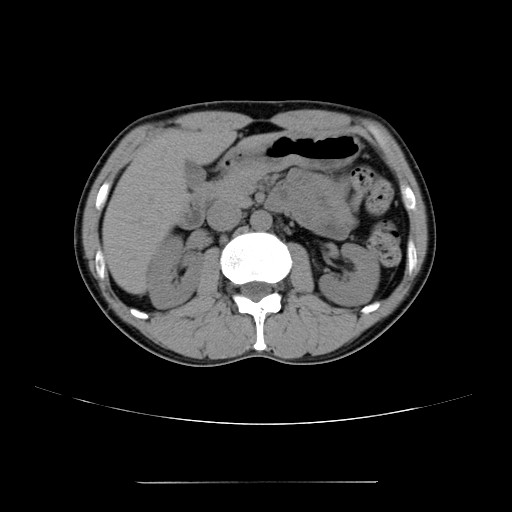

2006年入院治療の退院日から10年。 かなり大きな節目なんだが、なんだろうこの軽い感じは(笑)。 「10年生きたんだぁ」くらい。 変わったような変わっていないような。 当時は10年後なんて全く考えていなかった。 今も10年後は考えていないが・・・。 退院前日の2006/10/31は46.6kgだった。 今日計ったら54.8kg。体脂肪は16.6%。 とても健康にストレスなく生活できていることに、治療当時から現在に至るまで、関わった人全員に感謝の気持ちです。 マーカー、CT画像、問題なし!! 血液検査結果もほとんど文句なしの正常値。 そうだなぁ、数値に出ない異変としては、肩凝りかなぁ。 一旦夏になくなったと思ったが、初秋から再発。 マウスを左手にしたり、シップ貼ったり、最近はホッカイロ貼ったり。 で、一向に良くなる気配がない。 やはり四十肩なのか。 でも肩の可動域は問題ない。動かせないような痛みも無い。 結局色々考えてたどり着いたのは「変形性頚椎症」ではないかと。 肩凝りや頭痛がダラダラと続くようになるという症状がピッタリ当てはまる。 さて、改善策がなかなか難しい。 整形外科行ってもレントゲン撮って湿布をくれるだけだろう。 そんなことに大金を出すならまずは300円/回のプールで泳ごうと思う。 重力から開放して全身運動をするのが一番良いらしい。 2015年の目標は少しでも良いから水泳を再開する、だな。 マーカー、CT画像、問題なし!! 通常の血液検査結果も文句なしの正常値がズラ~っと並んだ!! 間違いなくヨメの食事のおかげである。ほんとうに感謝である!! ちなみに最近少々腰周りの肉付きが気になっていたのだが・・・。 左から2013年12月、2013年06月、2012年12月と背骨の位置は合わせて並べてみた。 6月まではあまり変化がなかったが、この半年で明らかに違う。 背中側の脂肪がやや増えてはいる。 でも最も大きな違いは、腸なのか、やたらと内臓が膨れている・・・。 一言で言うと食べすぎ?!?! 食事は野菜中心ではあるが、確かによく食べているw。 せっかくスーツのウエストを詰めたんだからこれ以上にならないようにしたい。 「腹八分目を心がける」かな。